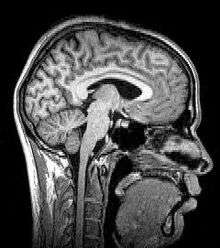

Para-sagittal MRI of the head in a patient with benign familial macrocephaly.

Sagittal MRI slice at the midline.

Magnetic resonance imaging (MRI) uses magnetic fields and radio waves to produce high quality two- or three-dimensional images of brain structures without use of ionizing radiation (X-rays) or radioactive tracers.